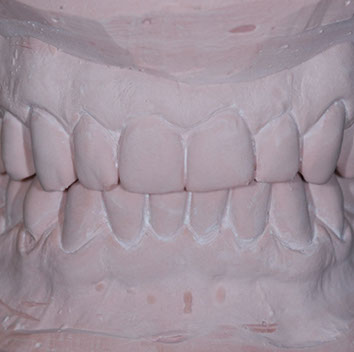

due impronte della bocca da cui si ricaveranno dei modelli in gesso

Nei ragazzi di età superiore (quando la maggior parte dei denti permanenti sono in arcata) e negli adulti, si interviene con trattamenti fissi mirati sia alla risoluzione delle malposizioni dentarie, sia alla correzione degli incongrui rapporti intermascellari in modo da allineare i denti e migliorare l'estetica raggiungendo una buona funzione masticatoria.